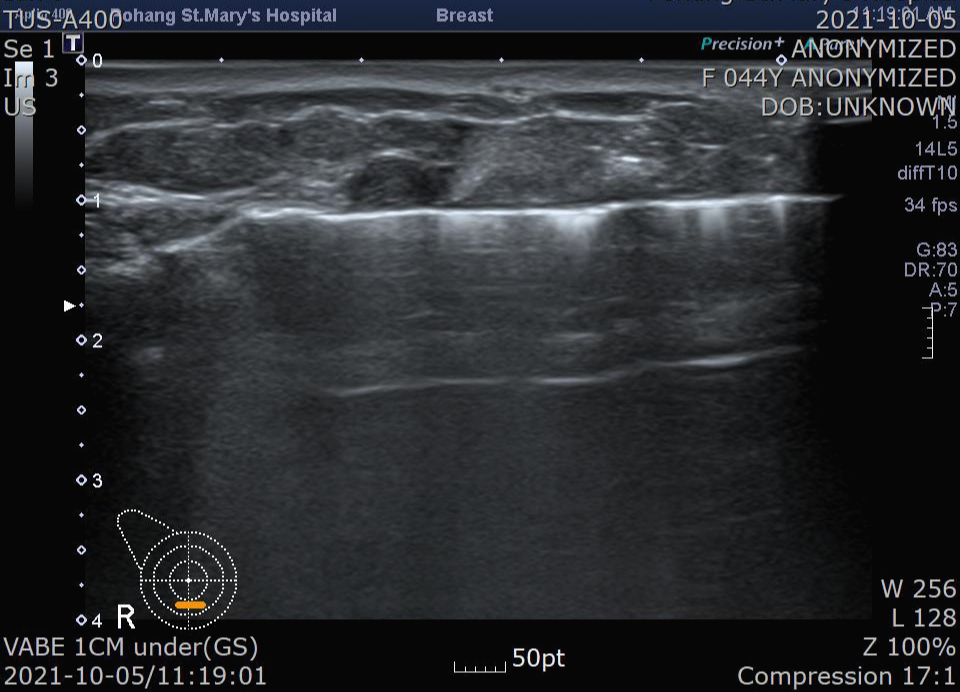

칼날을 닫으면서 조직을 자릅니다. 잘린 조직은 맘모톰 프루브를 통해 유방 밖으로 제거됩니다.

또 칼날을 엽니다.